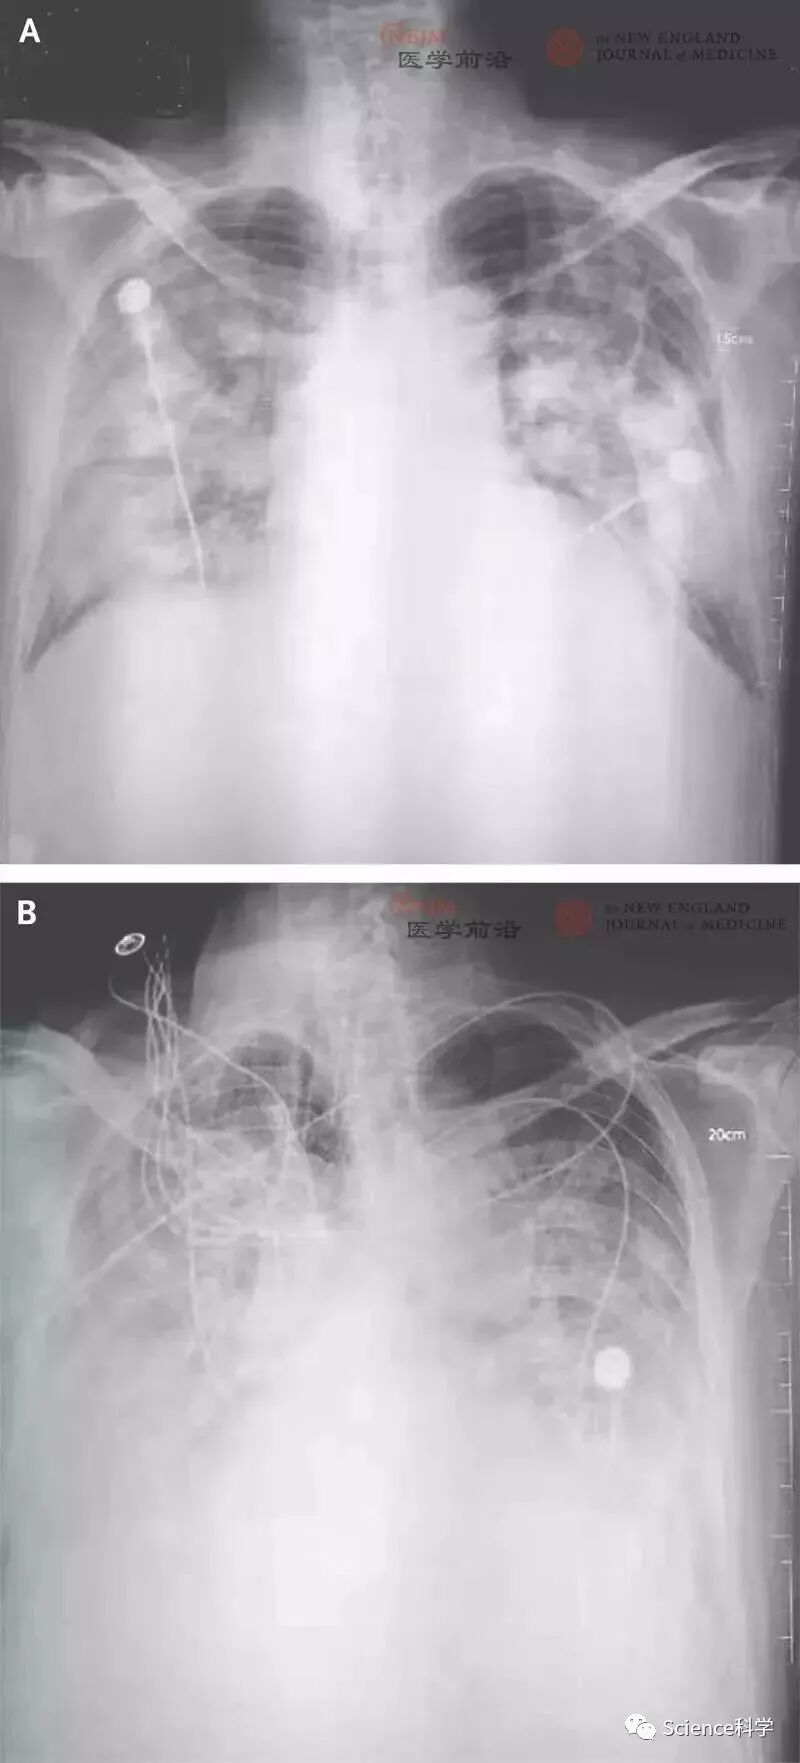

患者2初始症状从2019年12月20日开始,出现了发热和咳嗽。在起病后7天出现呼吸困难且后续2天进行性加重(胸片资料见图1),在此期间进行了机械通气。该患者曾经常出入海鲜市场采购。患者1和患者3在经过治疗后于2020年1月16日出院,但患者2在2020年1月9日死亡,没有采集到患者的组织标本。

胸 片